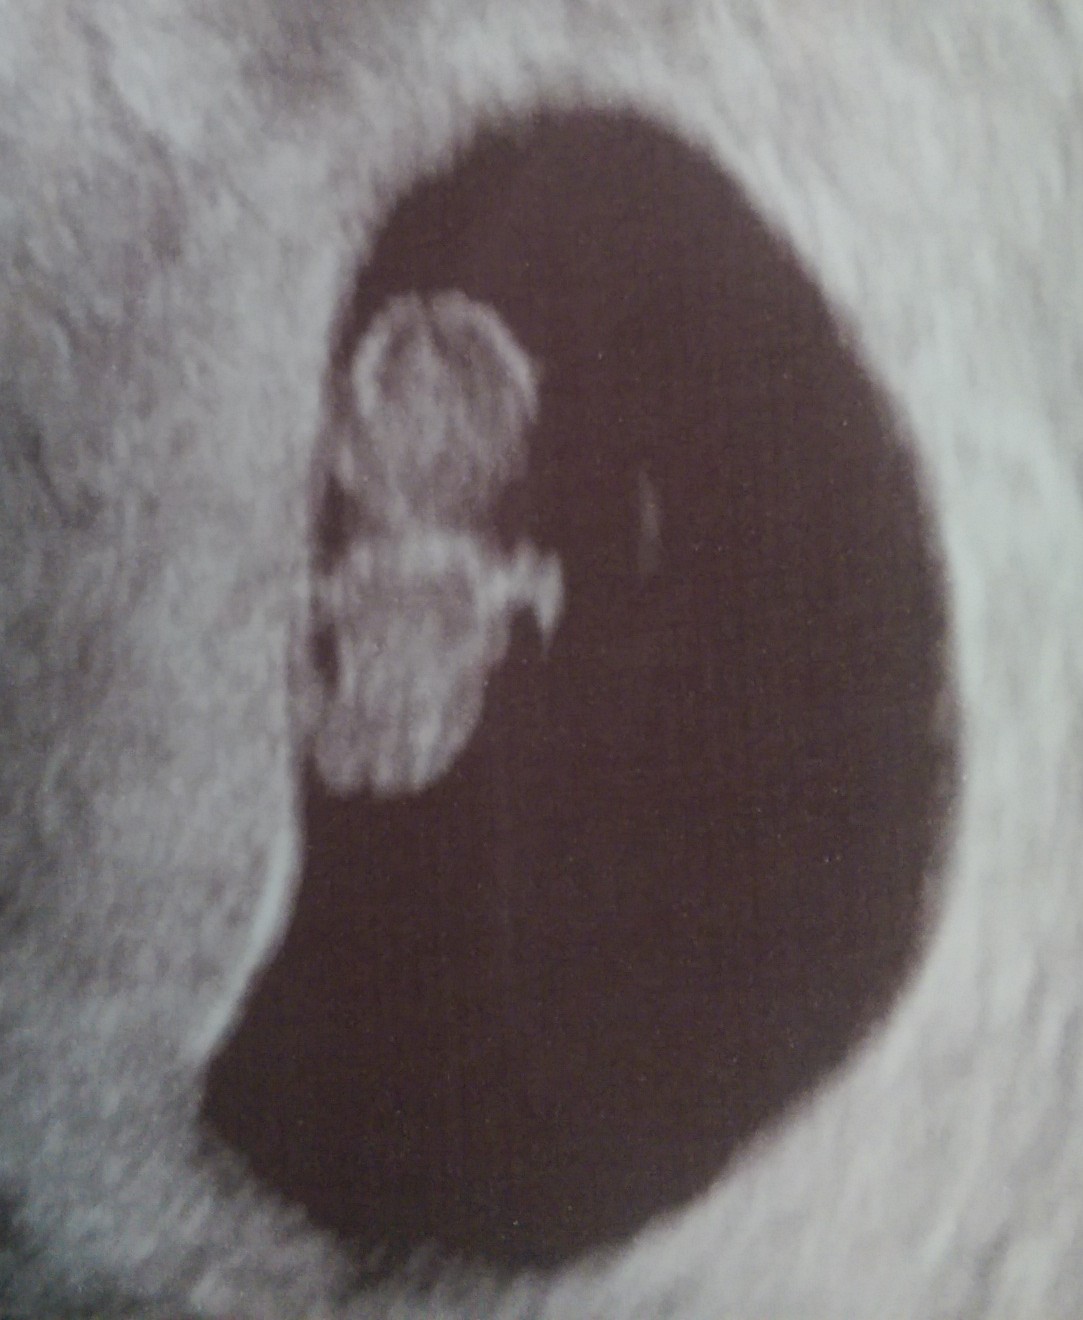

@sincerelymom I can't believe how well detailed you can see your little one in the first picture! I go Friday for my us and can not wait!

Yes, I was shocked myself! I think because they did a transvaginal they were able to do a 3-D pic. They actually gave me a few 3-D pics, but I picked my favorite for the post! Also- I am 10 1/2 weeks so baby is pretty big compared to a 6- or even 8-week u/s.